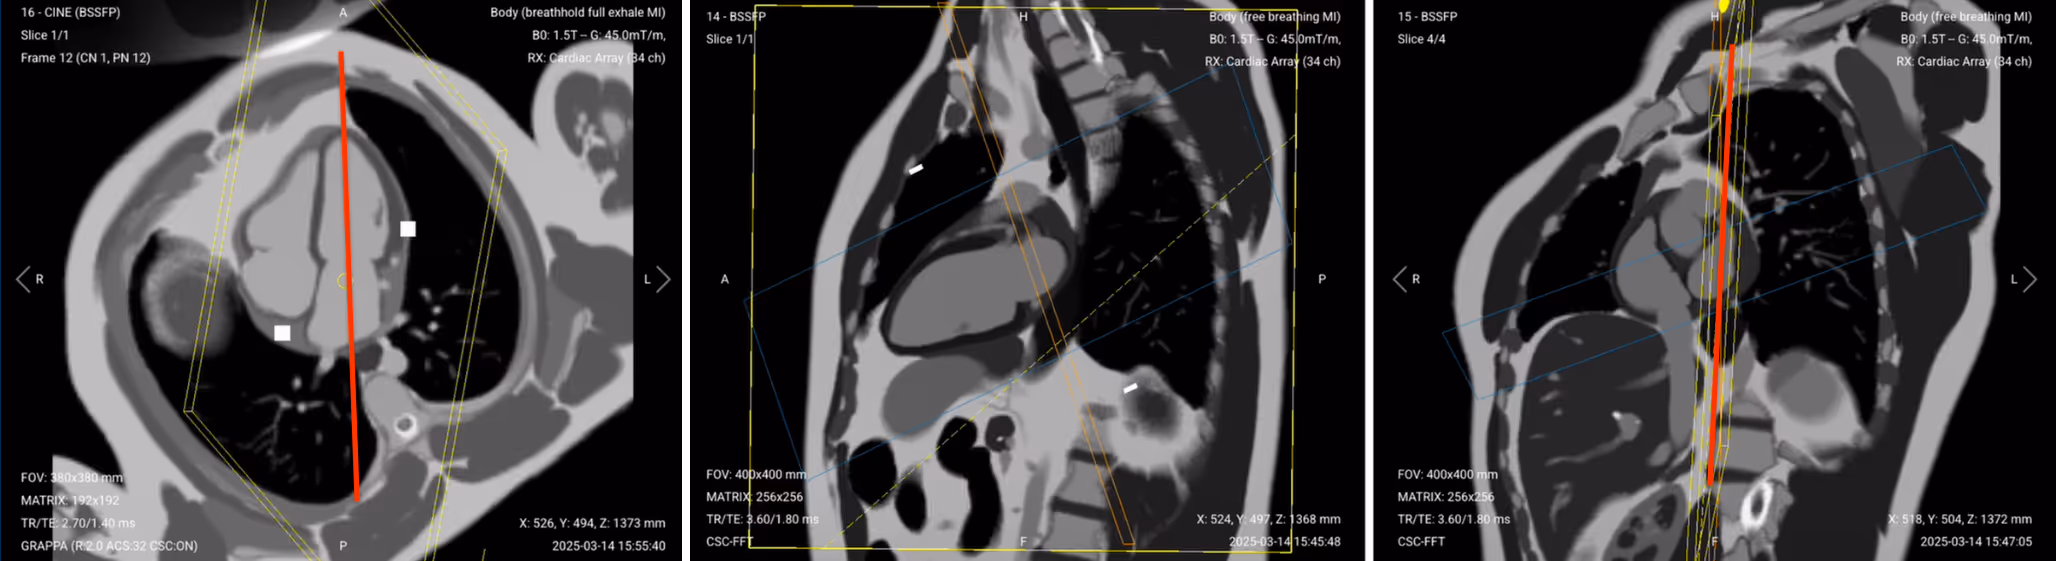

This diagnostic view shows all four heart chambers simultaneously, allowing assessment of their relationship.

✅ Correct Planning:

Planning Instructions:

Copy the slice position from the 2-chamber pseudo view as a starting point, then refine it to acquire the full 4-chamber view.

Use the mitral valve, left ventricle apex, and right ventricle apex as key anatomical references.

Align the slices as follows:

Axial localizer: Keep same as in pseudo 2-chamber. Ensure the slice passes through the mitral valve and continues to the apex of the left ventricle, forming a clean long-axis line through both left-sided chambers.

Sagittal 2-chamber pseudo: Adjust the slice to pass through the center of the mitral valve and extend down to the apex of the left ventricle.

Coronal SAX pseudo:

Tilt the slice so it runs below the aortic root and cuts through the right ventricle apex. Angle should intersect the full width of both atria and ventricles.

Scroll through coronal short-axis images to locate the slice where the left ventricular myocardium forms a complete ring (“black donut”). Make sure the 4-chamber cut passes through the center of this donut.

Confirm you see the classic “snowman” appearance: pulmonary artery (head), aorta (body), and left atrium (legs).

Set the fold-over direction (phase encoding) to anterior–posterior to reduce motion and metal artifacts, especially near implanted devices.

For patients with pacemakers or loop recorders, elevate the left arm above the head to reduce artifact interference during cine imaging.

✅ 4-Chamber Cine SSFP of the Heart – Correct Image Example:

Note that the 4-chamber cine image above shows a minor wrapping artifact at its top. But since it doesn’t interfere with the anatomy of the heart, it still meets diagnostic quality.

Things to Look for in 4-Chamber Cine: